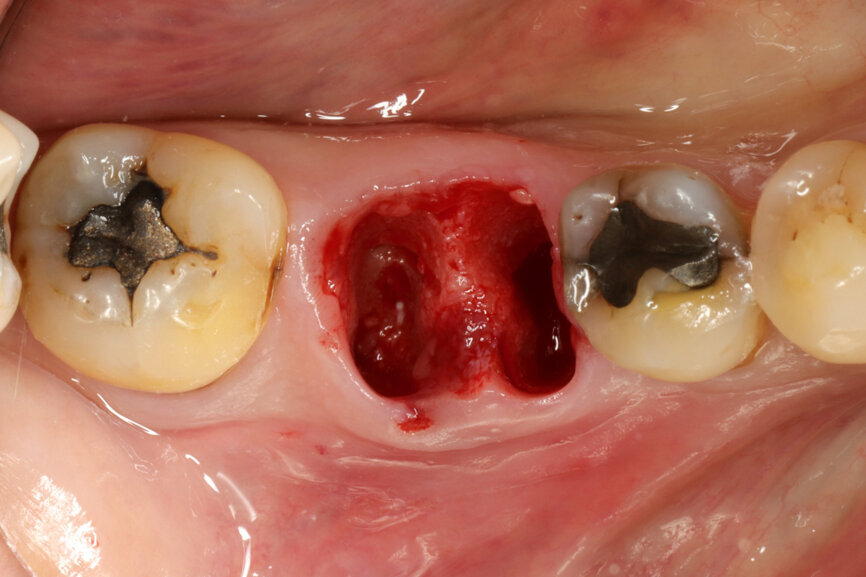

Fig. 4: Root splitting for minimally traumatic extraction.

Fig. 5: Socket dimensions preserved.

The surgical procedure was carried out under conscious sedation with local anaesthetic, and routine sterile preparations for surgical procedures were followed. To preserve the gingival and surrounding walls as far as possible, a flapless minimally traumatic approach to the extraction was employed by splitting the roots in different directions (Fig. 4). Extra precautions were taken not to inflict any trauma, not even by the suction device on the papilla and any surrounding soft tissue. A simple orthodontic elastic was placed around the adjacent teeth to delimitate the buccal and lingual red zone margins that should not be encroached upon.

It was possible to verify solid interradicular bone availability (Fig. 5), extending further the limits of the root apices and allowing for a centrally oriented osteotomy. The implant bed preparation started with the use of a needle drill at 800 rpm, followed by the ⌀ 2.2 mm and ⌀ 2.8 mm drills (Figs. 6–10). The implant was placed with the use of ratchet and torque control, reaching the desired final position at a 50 N cm torque value (Figs. 11–13). The socket was then augmented with bovine-derived bone substitute impregnated with advanced platelet-rich fibrin (A-PRF) and finalised with sutures to keep the A-PRF application immobile, and a 3 mm healing abutment was placed (Figs. 14–17).